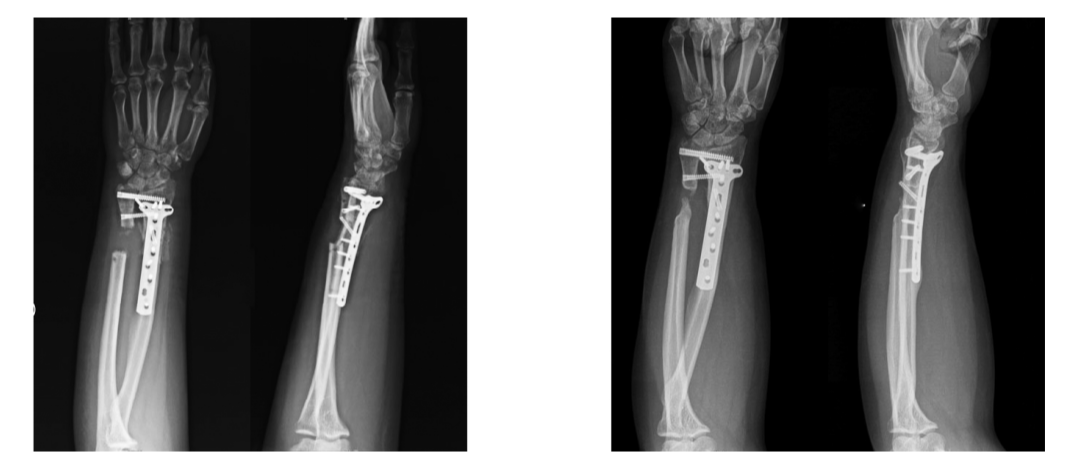

2.手术治疗对急性下尺桡关节脱位,可行克氏针固定尺桡骨:

对手法复位困难、复发性下尺桡关节脱位患者,可予以手术治疗。长期下尺桡关节脱位引起腕关节退变者,可予以尺骨小头切除,或Sauvé-Kapandji法重建下尺桡关节。在骨性结构完整的情况下,可予以重建韧带。

一例17岁患者,腕关节慢性疼痛3月,X线未见明显脱位(AB),MR检查提示下尺桡关节背侧脱位(C),予以下尺桡关节韧带重建(D),术后10年复查下尺桡关节位置良好,患腕无明显疼痛。